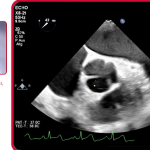

Sadri et al. present the first in-vitro study that compares a conventional valve with a rapid deployment valve in the same surrounding physiology. PERIMOUNT Magna Ease and EDWARDS INTUITY Elite valves were sequentially implanted in a donor heart, and μ-computerised tomography used to develop 3D-printed flow models for each valve. Sadri et al. explain how the EDWARDS INTUITY Elite, a rapid deployment valve, may increase effective orifice area and lower transvalvular pressure gradients, peak velocities and patient─prosthesis mismatch.